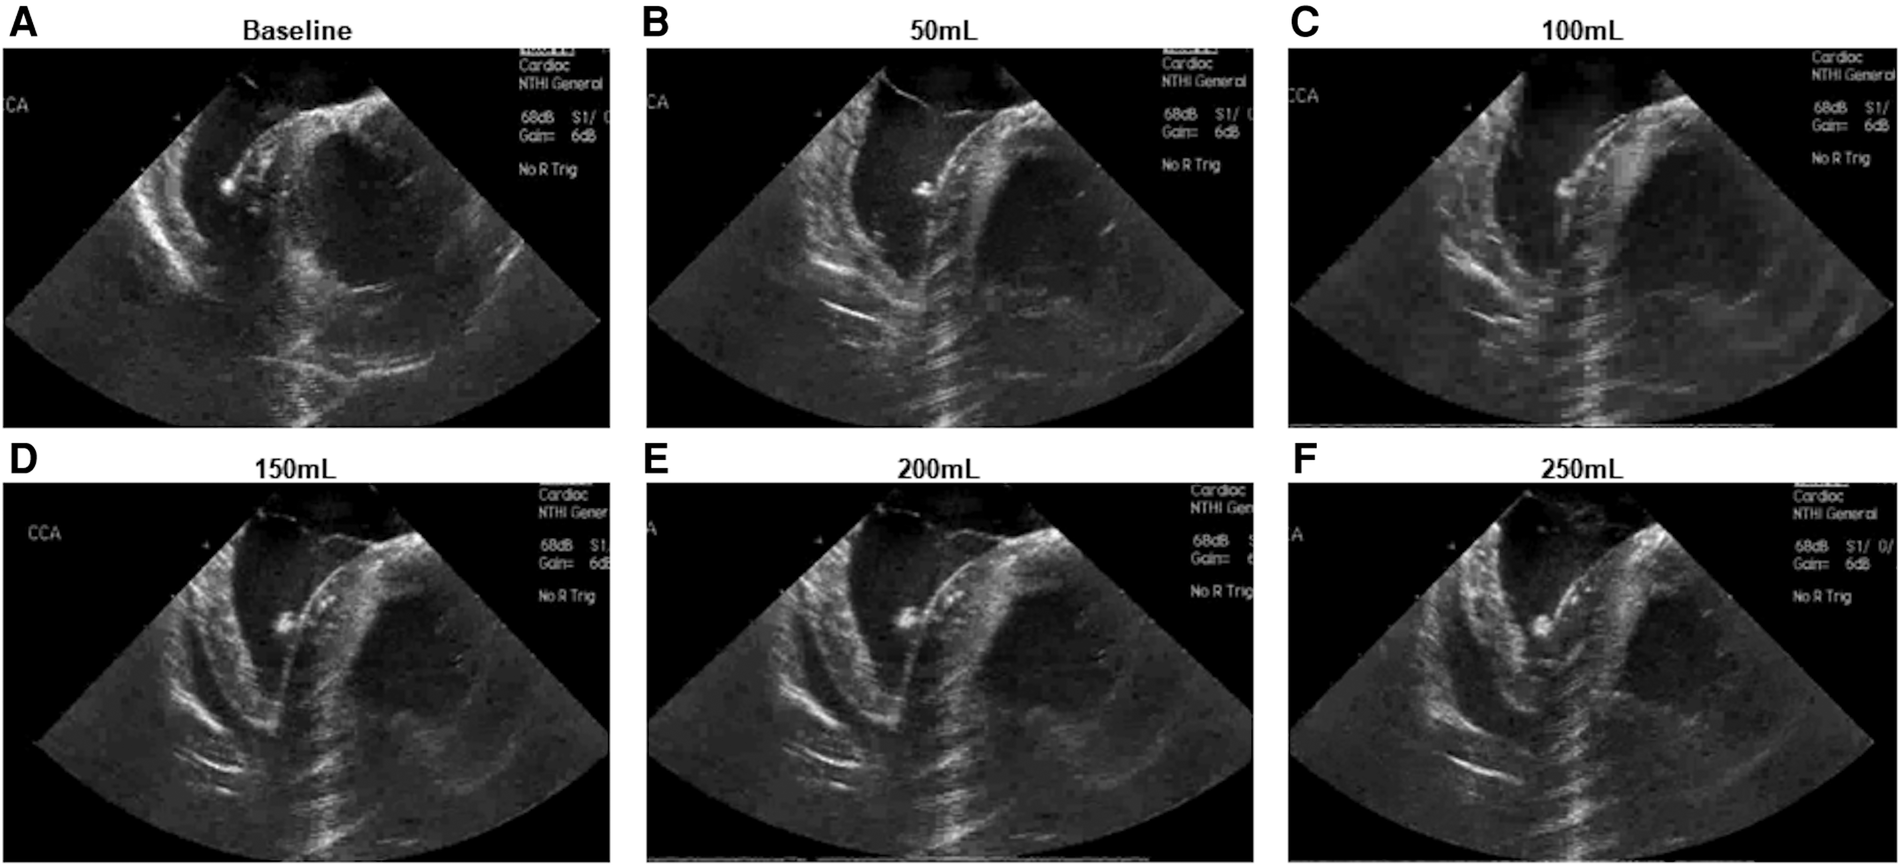

Intracardiac echocardiography was utilized to confirm successful creation of a pericardial effusion, with an observed increase in echocardiographic effusion as the volume of infused fluid increased (Figure 2).

Figure 2

Intracardiac echocardiographic appearance of developing pericardial effusion. (A) Baseline appearance (B–F) Appearance following infusion of (B) 50 ml (C) 100 ml (D) 150 ml (E) 200 ml (F) 250 ml.